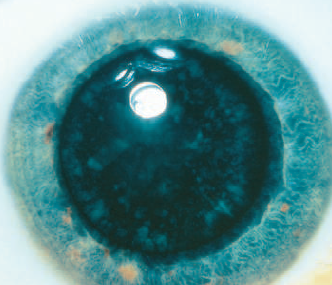

Cerulean

Cerulean sering dikenal sebagai katarak titik biru karena kataraknya berwarna biru langit dengan kekeruhan kecil berwarna kebiruan yang terletak di sekitar korteks lensa. Katarak cerulean bersifat non progresif, dan biasanya tidak menyebabkan gangguan penglihatan.